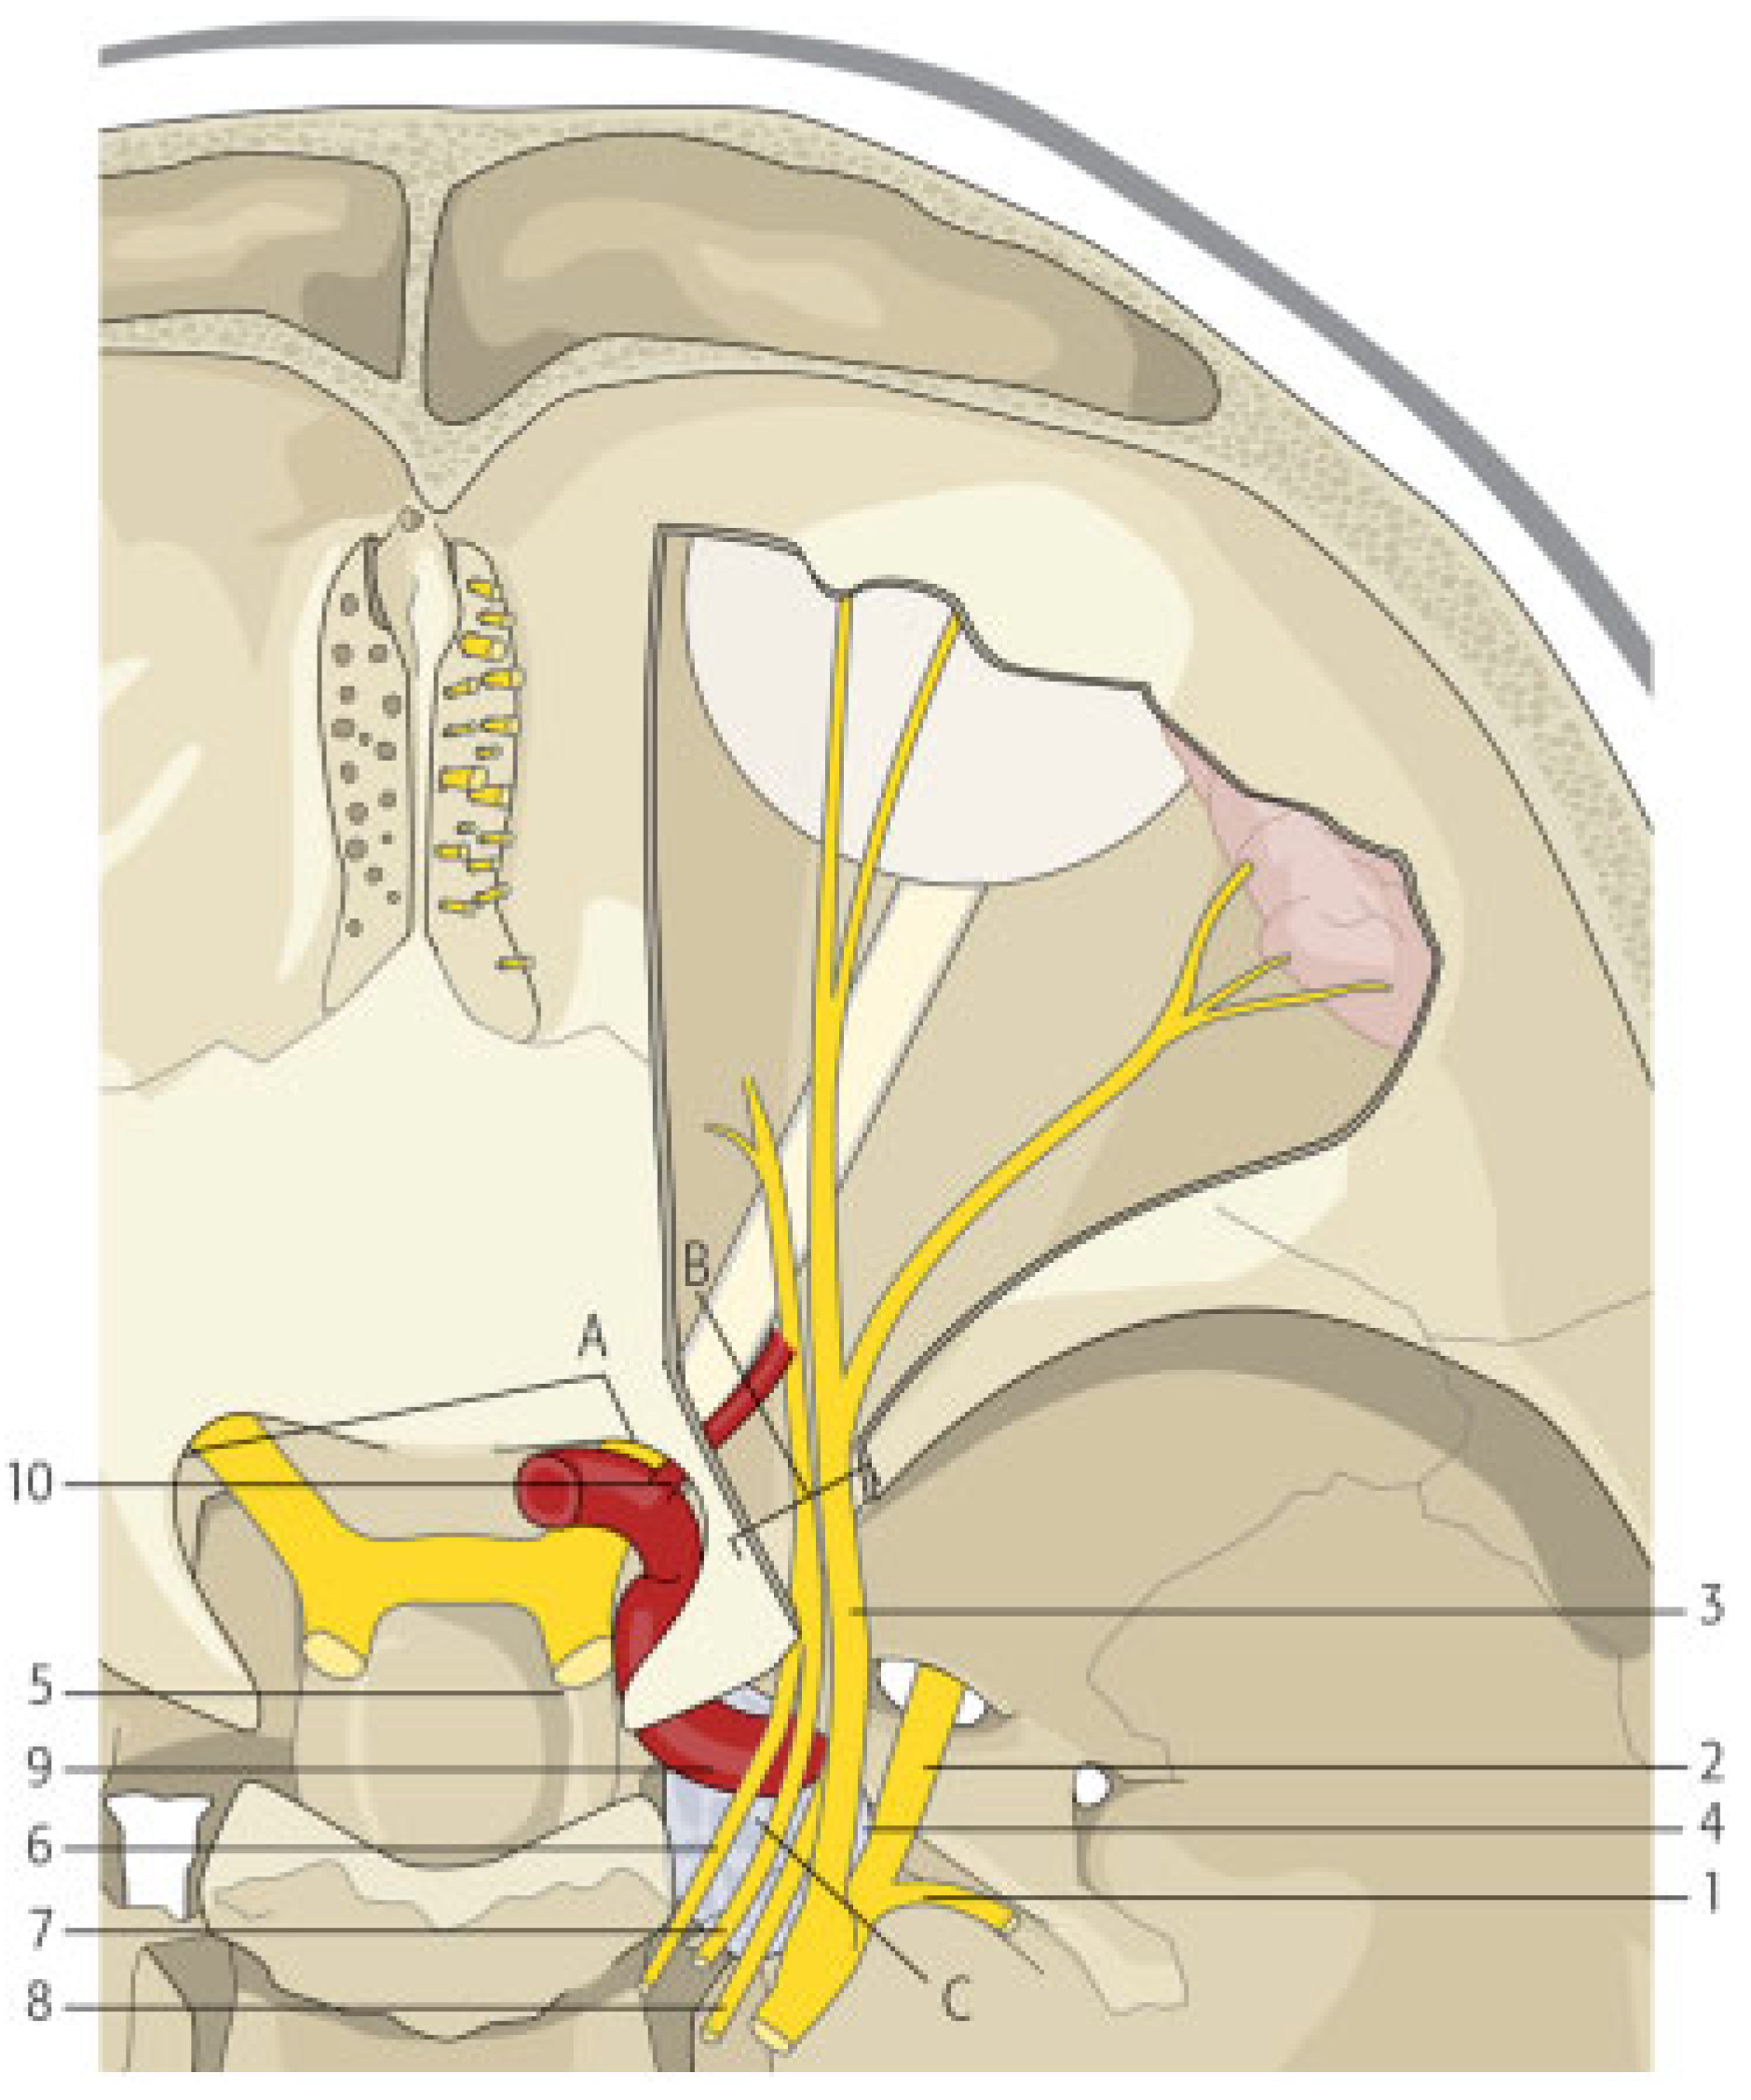

Figure 6. (a) Schematic drawing showing which structures pass through the cavernous sinus and are consequently affected in case of cavernous sinus syndrome or carotidcavernous fistula (1) oculomotor nerve, (2) trochlear nerve, (3) ophthalmic division of trigeminal nerve, (4) maxillary division of trigeminal nerve, (5) abducens nerve, (6) internal carotid artery, (7) cavernous sinus, (8) pituitary, and (9) sinus sphenoidalis. (b) Schematic drawing showing the superior orbital fissure and the optic foramen together with the structures that pass through each of them. In case of a fracture that involves the superior orbital fissure, structures that pass through the fissure into the orbit are usually affected. If the optic foramen is also involved, the patient also suffers from loss of visual acuity due to mechanical compression of the optic nerve or the central ophthalmic artery. (1) lacrimal nerve, (2) frontal nerve, (3) superior ophthalmic vein, (4) trochlear nerve, (5) oculomotor nerve superior branch, (6) abducens nerve, (7) nasociliary nerve, (8) oculomotor nerve inferior branch, (9) inferior ophthalmic vein, (10) optic nerve, (11) ophthalmic artery, (A) superior orbital fissure, (B) optic foramen.